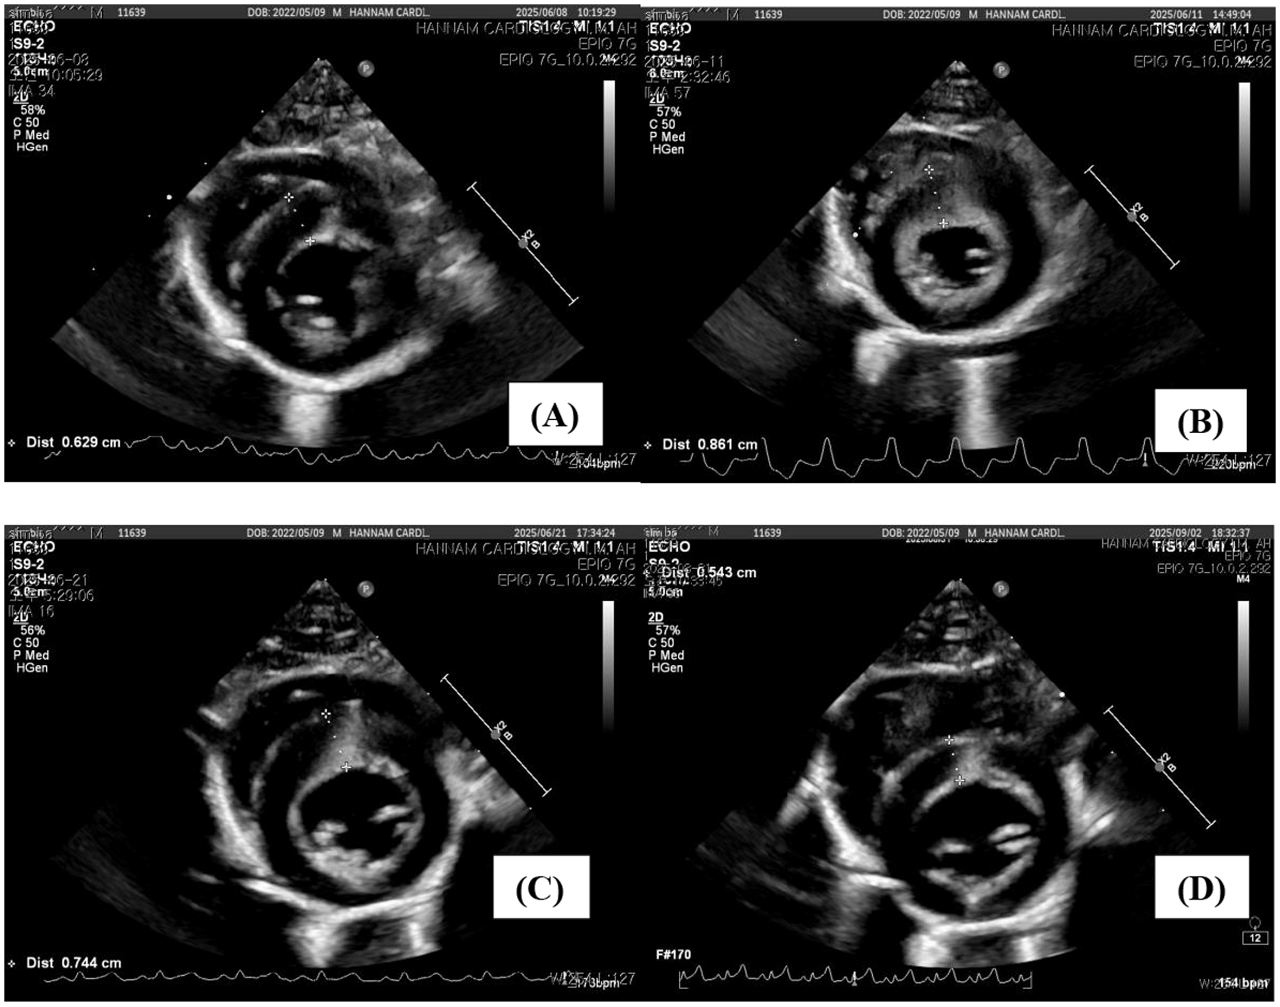

초기 입원치료로 전신 상태와 간 수치는 개선되는 추세를 보였지만, 3일차의 재평가에서 예기치 못했던 심장 지표의 급격한 악화가 확인됐다. 심장 트로포닌I(cTnI)이 급격히 상승했고, NT-proBNP는 측정 상한치를 초과할 정도로 치솟았다. 심초음파에서도 현저한 심실중격 비후와 좌심실 유출로 폐쇄(LVOTO)가 관찰됐다.

심장초음파(좌심실 단축면)에서 측정한 심근두께가 내원 3일차에 최대 8.6 mm까지 증가했다가, 임상 증상 호전과 함께 5.4 mm로 감소하며 정상 두께로 회복되는 경향을 보였다.